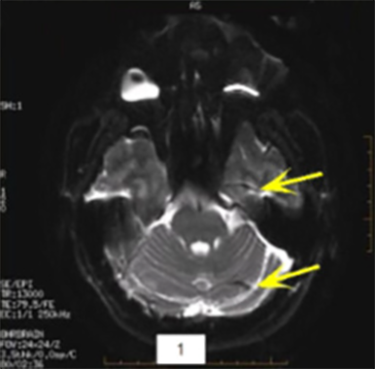

| DWI/DTI Ring Ring-like artifact | ![]() | Intense orbit signal |